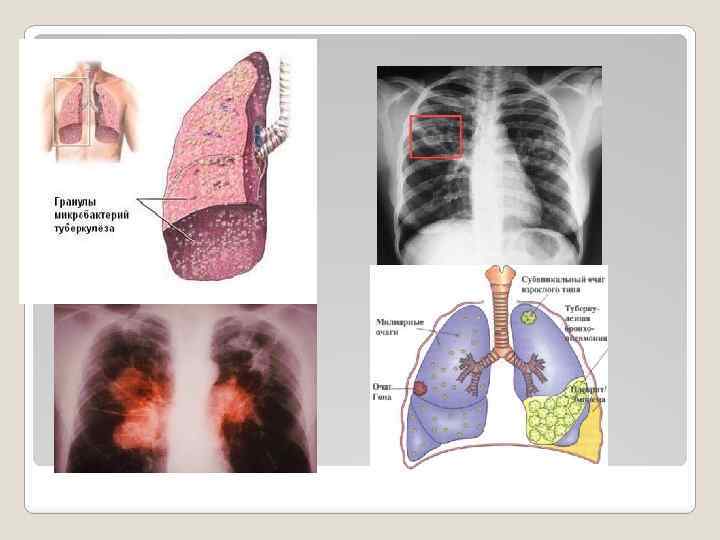

ТУБЕРКУЛЕЗ Бұл ауа-тамшыларымен таралатын жұқпалы ауру және aғзағa туберкулез бактериялары түскенде дамиды. Ең алдымен өкпе, кейде басқа органдарды да зақымдайды. Жұқтыру көзі туберкулезге шалдыққан адам болып табылады. ТУБЕРКУЛЕЗ НЕЛІКТЕН КАУІПТІ АУРУ БОЛЫП ТАБЫЛАДЫ жыл сайын 8, 8 миллион адам туберкулезбен аурады; ем қабылдамаған әpбip науқас жылына 10 адамнан 15 адамға дейін жұқтыруы мүмкін; туберкулезге шалдыққандардың 75% 20 -40 жас аралығындағы адамдарды кұрайды; оның салдарынан жыл сайын 2 миллионға жуық адам қайтыс болады; ауруды жұқтырғандардың 5 -10%-ында ғaнa ауру дамуы мүмкін.

ТУБЕРКУЛЕЗДІ ЖҰҚТЫРУ ҚАЛАЙ ЖҮРЕДІ Туберкулез қоздырғыштары ауру адам сөйлегенде, жөтелгенде, оқығанда, түшкіргенде бактерия шығару арқылы ауаға тарайды. Ауаның жұтқан адамдарға бактерия жоғарғы тыныс алу жолдарына, өкпелеріне түседі. Осылайша туберкулезді жұқтыру жүреді. АДАМ АҒЗАСЫНА ТУБЕРКУЛЕЗ БАКТЕРИЯЛАРЫ ТҮСКЕН КЕЗДЕ ЕҢ МАҢЫЗДЫСЫ МЫНАЛАР: - инфекцияның массивтылығы, доза, адам ағзасына туберкулез бактериялар түсуінің ұзақтылығы; - иммунитеттің туберкулез бактерияларына қаншалықты дайындығы. ӘРІ ҚАРАЙ НЕ БОЛАДЫ? Туберкулез бактериялары кез келген ағзада дами алады, бірақ көп жағдайда өкпенің жоғарғы жақтарында дамиды. 2 -10 апта ішінде ағзаның иммундық жүйесі микробактериялардың таралуы мен әрі қарай дамуын тоқтатады.